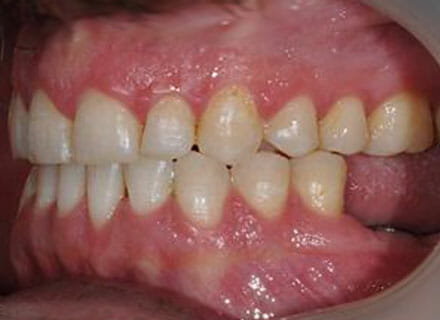

Big gaps and missing back teeth

This is a case where orthodontics and dental implants were used. First we closed the big gaps at the front using a fixed clear brace (this took under 12 months. Then we added 2 new teeth on the lower right where the premolar and molar were decayed right through using dental implants. Here the after pics were taken before the new implant teeth were added lower right.